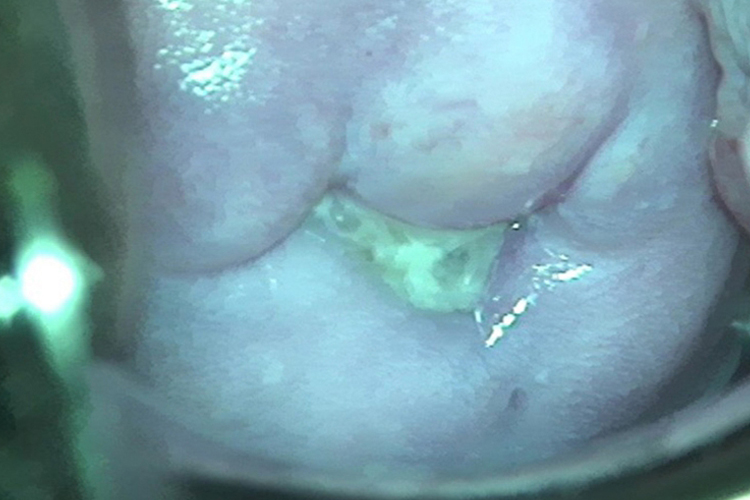

急性宫颈炎:患者主要表现为阴道分泌物增多,呈黏液脓性,宫颈上可观察到,阴道分泌物刺激可引起外阴瘙痒、灼烧感。此外,可出现经间期出血、性交后出血等症状,合并尿路感染可出现尿急、尿频等症状。

滴虫性阴道炎:滴虫性阴道炎患者的主要症状为白带增多,阴道分泌物呈灰黄色、乳白色或黄白色稀薄液体,或为黄绿色脓性分泌物,常呈泡沫状,有腥臭味。严重时白带可混有血液。多数患者有外阴瘙痒、灼热、性交痛等症状。有尿道感染时可有尿频、尿痛甚至血尿。